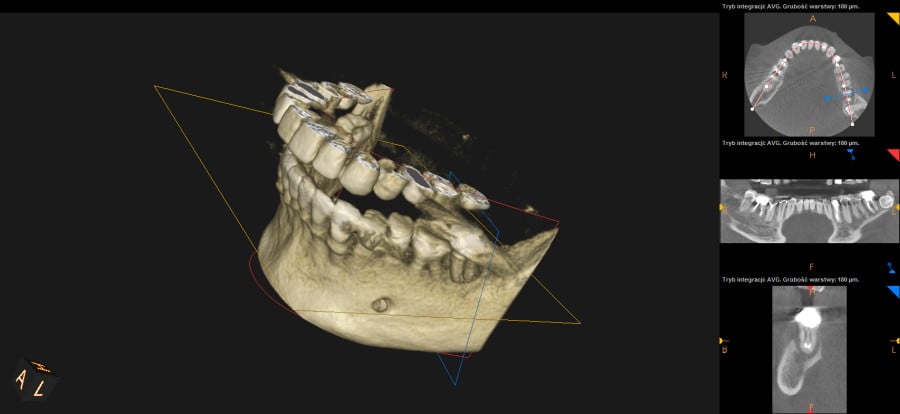

Ten problem najczęściej dotyczy zębów trzonowych żuchwy oraz górnych przedtrzonowców. Może również towarzyszyć wadom zgryzu, w zębach zniszczonych przez erozję, abrazję lub atrycję. Pionowe złamanie korzenia jest trudne do zdiagnozowania. Zdjęcia RTG nie zawsze bowiem ukaże „całą prawdę”. Coraz powszechniej używane obrazowanie CBCT (3D) pomaga w postawieniu diagnozy pionowego złamania zęba lub korzenia.

Do pionowego złamania korzenia zęba może dojść podczas zabiegu leczenia kanałowego poprzez używanie zbyt dużej siły w czasie wypełniania lub oczyszczania kanału. Może być również spowodowane zaklinowaniem się narzędzia w kanale. Pionowe korzenia zęba zawsze prowadzi do usunięcia całego zęba. Dbałość o profilaktykę i terminowe zgłaszania się do gabinetu stomatologicznego z towarzyszącą diagnostyką rentgenowską znaczącą redukuje te ryzyka.